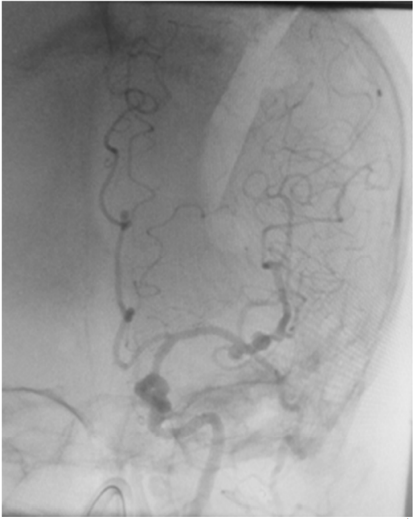

Uma paciente de 66 anos de idade, tabagista, hipertensa com tratamento irregular. Apresentou cefaleia súbita de severa intensidade associada a náuseas. Ao exame físico, observaramse AC = RR2T com BNF, FC = 100 bpm, AP = MVF sem RA, FR = 15 irpm, PA = 182 mmHg x 100 mmHg, SatO2 em ar ambiente = 97%, Glasgow 15, pupilas isofotorreagentes, sem deficits focais. TC crânio e arteriografia a seguir.

Fonte: Acervo pessoal.

Acerca desse caso clínico e com base nos conhecimentos médicos correlatos, julgue os itens a seguir.

Segundo a classificação da World Federation of Neurological Societies (WFNS), a paciente seria classificada como grau 1.